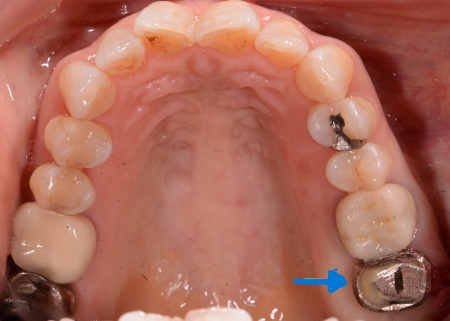

拝見したところ、左上の一番奥の歯(第2大臼歯)には金属の被せ物が装着されていました。

まず、左上の奥歯を抜くと同時にインプラントを埋め込む抜歯即時埋入を行います。

これは、歯を抜いた直後のあごの骨に人工歯根を埋め込む治療方法です。

事前のレントゲン検査で骨の状態を確認し、インプラントを埋め込む位置や角度を慎重に検討したうえで処置しました。

その後、歯ぐきやあごの骨が回復するまで一定期間待ち、インプラントが骨としっかり結合しているかを確認しました。

問題がないことを確認したうえで歯の型取りを行い、インプラントの上に装着する人工歯を作製しています。

最後に完成した人工歯を取り付け、噛み合わせに問題がないかなどを確認し治療を終了しました。